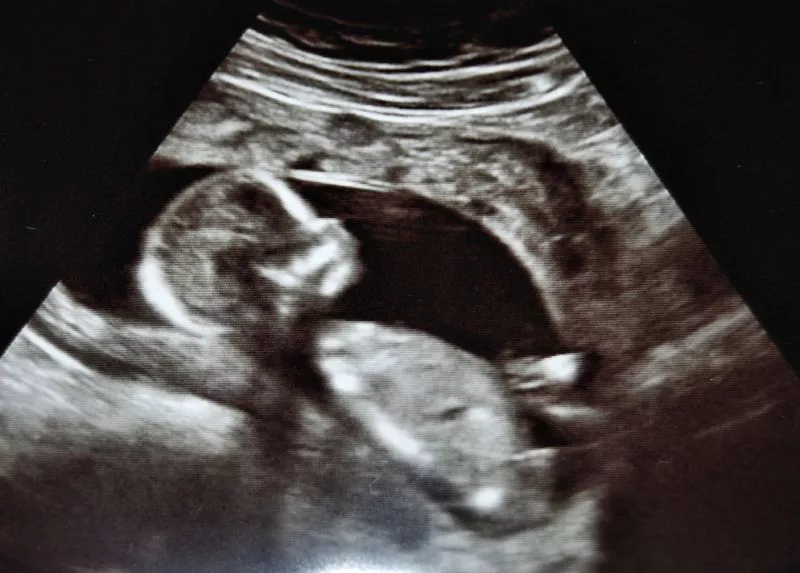

A newly developed acoustic rectifier could improve the image quality of sonograms (Photo: myllissa via Flickr)

Sonography, or ultrasound imaging, is commonly used for diagnostic and therapeutic applications – the best-known example being photos and videos of developing fetuses that expectant parents excitedly wave around. Because ultrasound relies on sound waves being sent into the body and then reflected back to create the image, the interference creating by these waves meeting causes some degradation of image brightness and resolution. In order to enable stronger, sharper medical imaging, scientists at Nanjing University in China have developed an "acoustic rectifier" that forces sound waves to travel in only one direction.